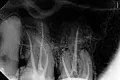

Здравствуйте, у меня периодически возникает ноющая боль справа, которая отдает в висок и под глаз, в район гайморовой пазухи. По моим предположениям, меня беспокоит 6 верхний зуб справа, нерв удален, на нем стоит мост. Врач говорит, что не в нем проблема, каналы хорошо запломбированы, надо искать причину в лор органах. По снимку можете сказать, так или это? Такое впечатление, что каналы не до конца пломбированы, и все ли запломбированы вообще. В этом зубе может быть до 5 каналов, помогите разобраться. Какие мои дальнейшие действия?

Добрый день, Алла. Ваш доктор не прав, на верхушках двух корней имеется грануляционный воспалительный процесс. Данное воспаление - следствие некачественного лечения каналов, но проблема имеет давние корни, то есть данной проблеме 2-5 лет.

Обратитесь к грамотному терапевту, если вы запустите ситуацию, то зуб можете потерять. Всего вам доброго.